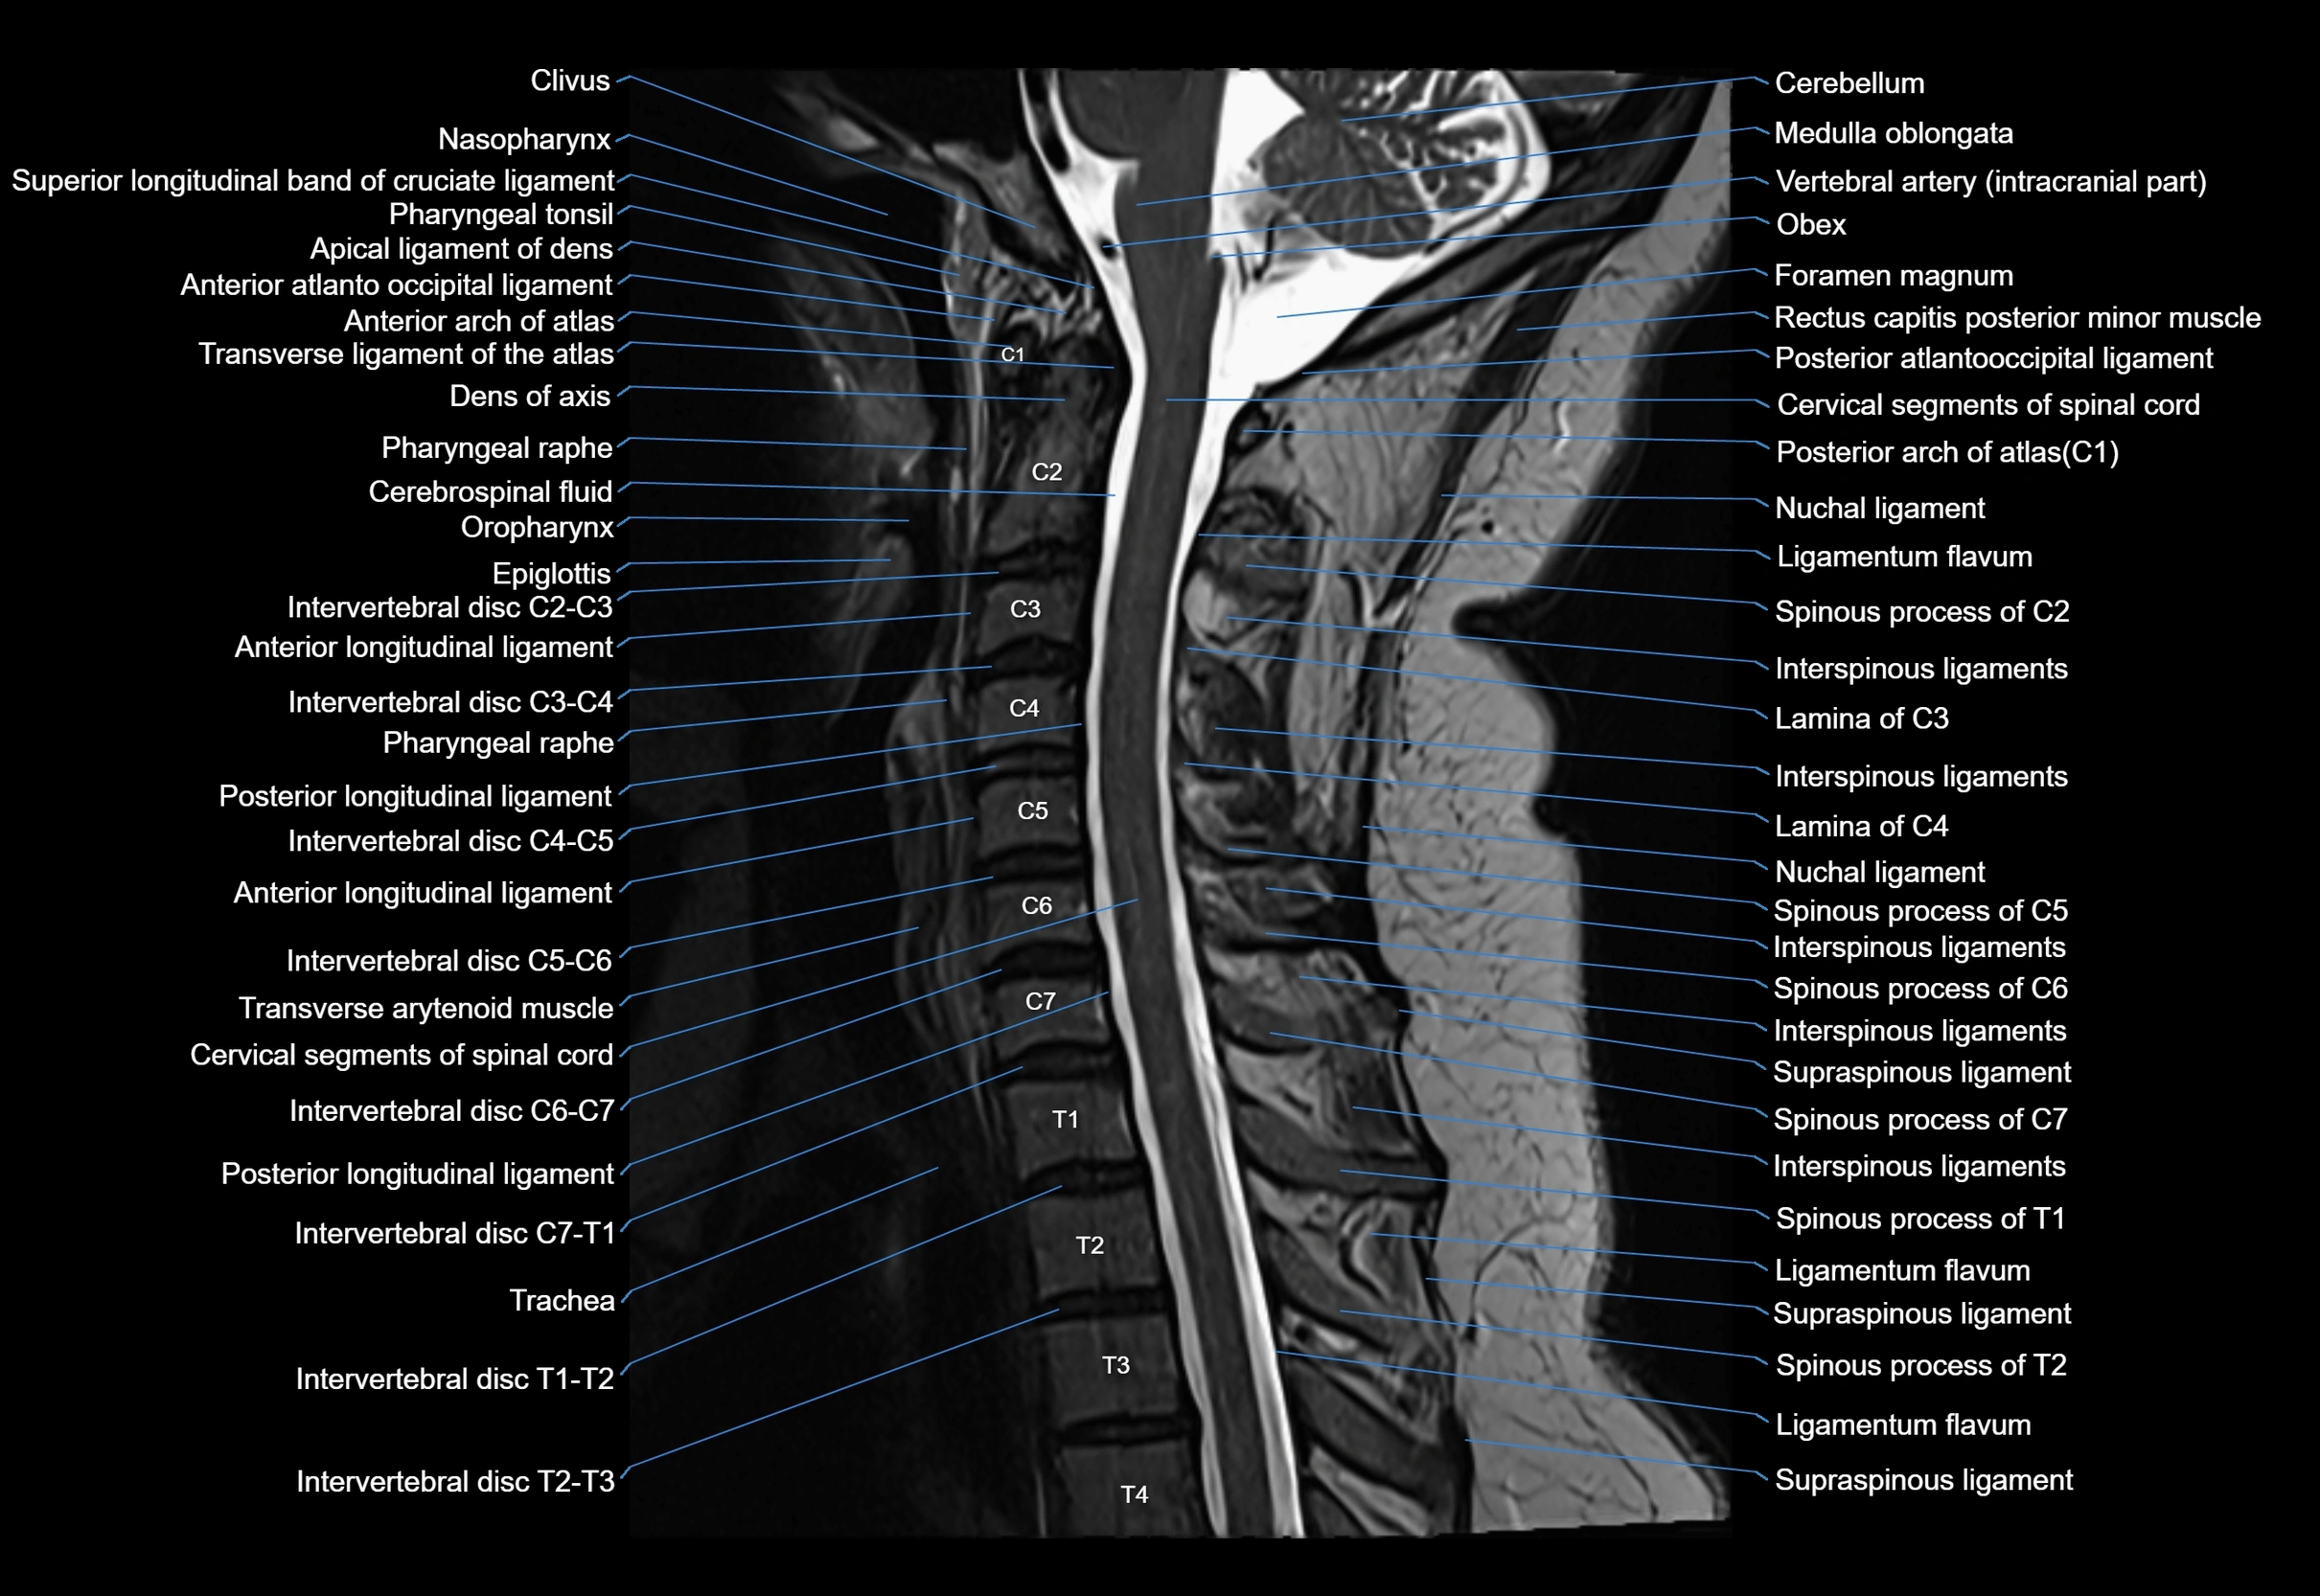

MRI image

image